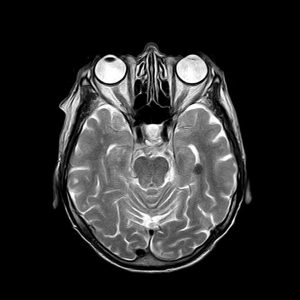

S’est alors produit quelque chose d’aussi inattendu que déterminant, lorsqu’au début des années 1990 un petit groupe de chercheurs, de psychothérapeutes et de « psychonautes », convaincus que la science et la culture avaient délaissé une précieuse découverte, ont discrètement décidé de se la réapproprier. Après plusieurs décennies de répression et d’oubli, les psychédéliques connaissent aujourd’hui une renaissance. Une nouvelle génération de scientifiques, dont bon nombre inspirés de leur propre expérience, investiguent l’efficacité potentielle de ces substances dans le traitement d’affections mentales comme la dépression, l’anxiété, les traumatismes et les addictions. Dans le même temps, d’autres chercheurs associent les psychédéliques à de nouvelles méthodes d’imagerie cérébrale pour explorer les liens entre le cerveau et l’esprit afin d’élucider certains des mystères de la conscience.

/forum/uploads/images/1582/irm-cerveau-recherche-300x300.jpgLes scientifiques cherchent à comprendre les effets des psychédéliques sur le cerveau

Une bonne manière de comprendre le fonctionnement d’un système complexe est de le perturber et d’observer les conséquences. Quand on provoque des collisions entre atomes, un accélérateur de particules les force à révéler leurs secrets. De façon similaire, en administrant des psychédéliques précisément dosés à un patient, les neuroscientifiques peuvent profondément perturber l’état de conscience ordinaire de leur sujet au point d’entraîner une dissolution de l’ego et de provoquer ce que l’on appelle une « expérience mystique ». Pendant l’expérience, des appareils d’imagerie enregistrent les changements intervenus dans l’activité cérébrale et les modes de transmission synaptique. Ces travaux donnent déjà un aperçu surprenant des « corrélats neuronaux » de la conscience de soi et de l’expérience spirituelle. Le cliché éculé des années 1960 selon lequel les psychédéliques permettent de comprendre et d’ « élargir » la conscience ne paraît dès lors plus si ridicule. »